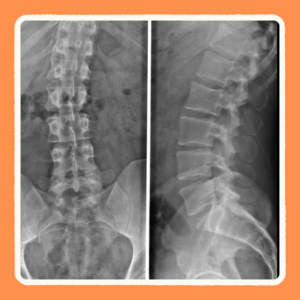

側弯症の診断は、まず視診や触診で確認します。学校での運動器健診や整形外科で行われる「前屈検査」で異常を見つけることが多いです。

確定診断にはX線検査が必要で、背骨の曲がり具合を「コブ角」という角度で測定します。

• 軽度:20度未満

• 中等度:20〜40度

• 高度:40度以上

診断方法

確定診断にはX線検査が必要